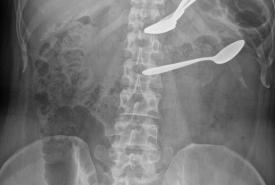

Successful Conservative Management of Multiple Spoons Ingestion in a Psychiatric Patient - An Unusual Case Report